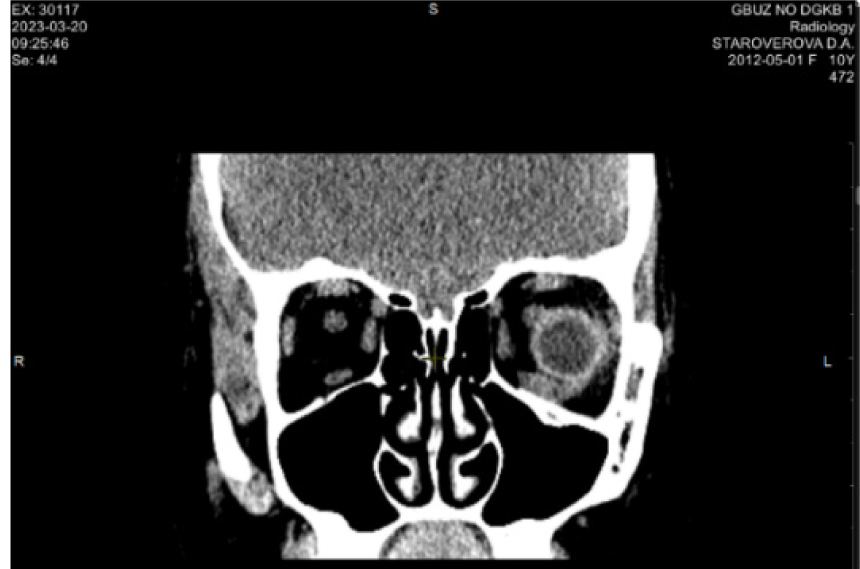

Клинический пример 1. Родители пациентки С. 10 лет обратились с жалобами на ограничение подвижности левого глаза вверх и двоение. Из анамнеза известно, что неделю назад девочка ударилась головой при падении. По данным компьютерной томографии (КТ), слева имеется трещина нижней стенки орбиты в средней трети шириной 2 мм. В зоне локализации перелома – дефект нижней прямой мышцы, предположительно разрыв, пролапс мягких тканей орбиты в верхне-челюстную пазуху до 9 мм. При объективном осмотре в первой позиции взора выявлена ортотропия и полное отсутствие подвижности левого глаза кверху (рис. 1). Пациентке поставлен диагноз: перелом нижней стенки орбиты, разрыв нижней прямой мышцы. Рекомендована ревизия зоны перелома и нижней прямой мышцы cito.

По данным КТ: фиброзное утолщение нижней прямой мышцы слева, пластинка выполняет контур нижней стенки глазницы (рис. 4).

Рис. 4. Компьютерная томография орбит через год после операции. Клинический пример 1